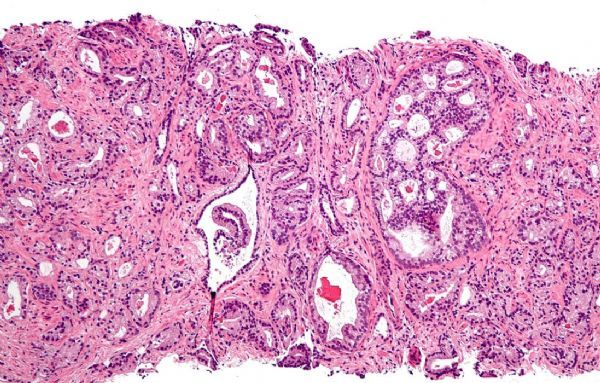

深入解读前列腺癌的新型疗法和筛查手段的进展状况

2018年3月23日 讯 /生物谷BIOON/ --近日,发表在国际杂志the Journal of Clinical Oncology上的研究报告中,来自美国西北大学综合癌症中心的研究人员通过研究描述了恶性前列腺癌疗法的最新研究进展情况,同时研究人员呼吁采用一种平衡的方法来进行疾病的早期诊断

大部分前列腺癌患者并不会死于前列腺癌,然而转移性去势抵抗性前列腺癌(mCRPC,metastatic castration-resistant prostate cancer)患者的预后往往较差,在这类前列腺癌中,患者机体的癌症常常会扩散到其它部位,尽管患者采用了激素疗法但病情仍然会发生进展。目前很多科学家非常感兴趣开发治疗前列腺癌患者的新型治疗手段,而该领域就是研究者Hussain非常感兴趣的一个研究领域。